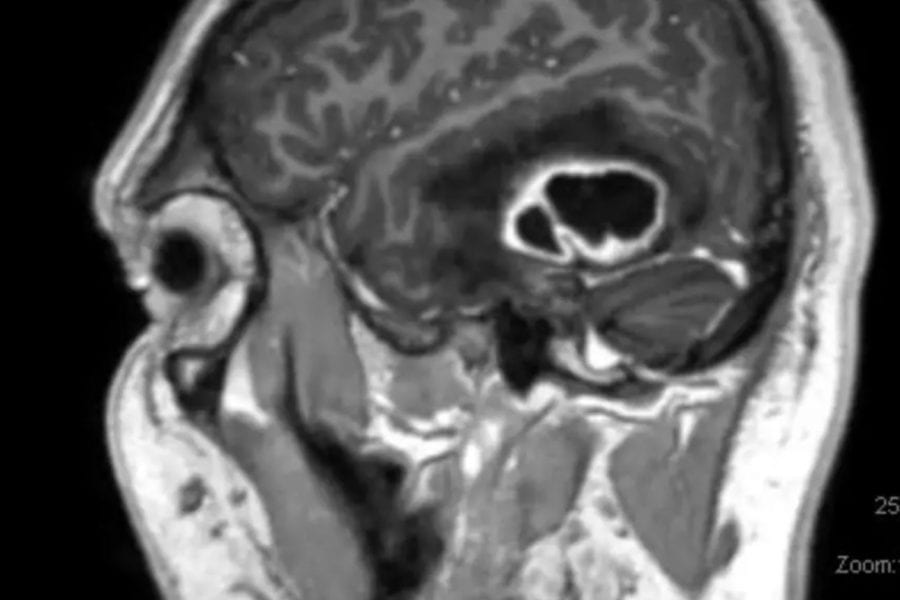

New scanning technology is being used to help doctors operate on back pain patients with greater confidence and precision. St Vincent's Private Hospital in Sydney…